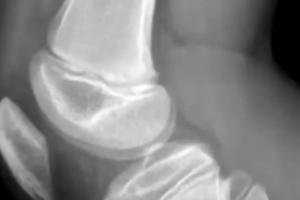

受傷孩子母親張女士告訴荔枝新聞 ,他們老家在陜西西安,2024年2月特意帶孩子前往大連加入“嗨球”青訓(xùn),每天除去上學(xué)、寫作業(yè),訓(xùn)練時(shí)間至少4小時(shí)左右。在較高的強(qiáng)度之下,孩子膝蓋受傷,有“脛骨結(jié)節(jié)炎、髕腱炎、骨裂”,教練的一些不當(dāng)言語也給孩子造成心理傷害,因而產(chǎn)生退出的想法,卻被索要高額賠償才能換取“自由身”。